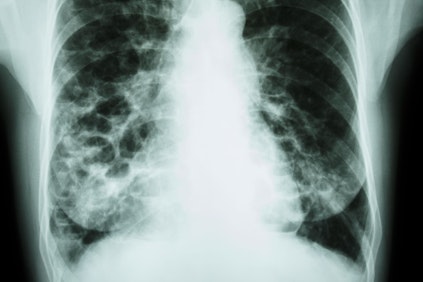

Comprehensive Care for a Diverse Range of Lung Conditions